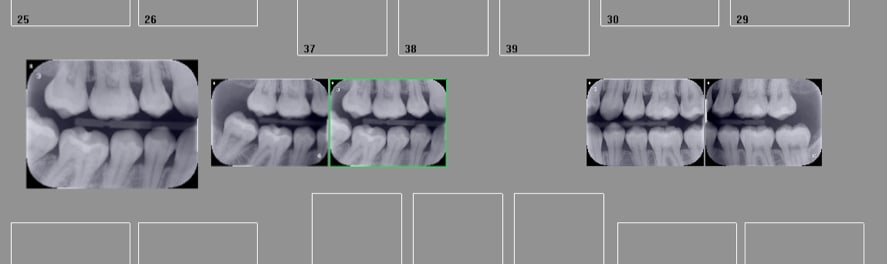

Capture d écran 2017 07 03 21.01 - Eugenol

Et ca ca vaut quoi ?

Capture d écran 2017 07 03 21.08 - Eugenol